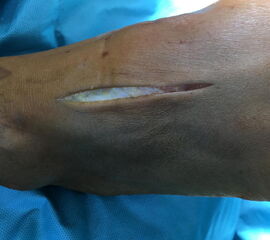

• Hautschnitt lateral / medial der A.dorsalis pedis über dem II./III. Tarsometatarsalgelenk (Abb. 13).

• TIPP: Markierung der A. dorsalis pedis vor der OP auf dem Fußrücken, um beim Zugang sicher medial oder lateral des Gefäß-Nervenbündels einzugehen (Abb. 12).